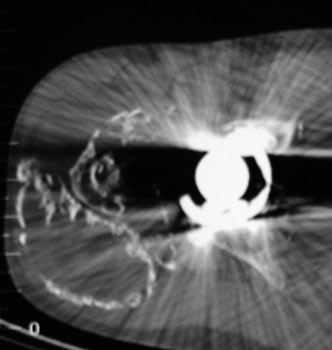

HETEROTOPIC BONE FORMATION adjacent to loose femoral component, plain film and CT